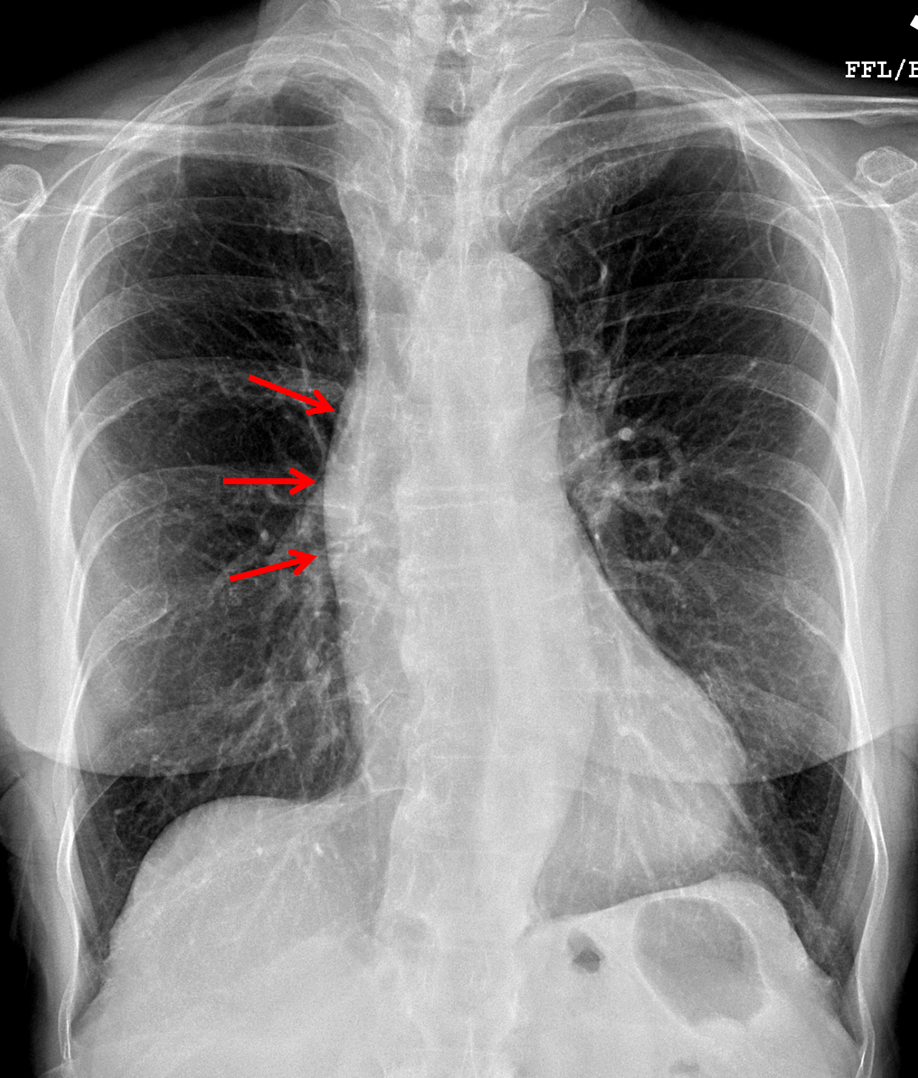

Age: 83

Sex: Female

Indication: Chest pain

Sample ReportFindings concerning for dilation of the ascending aorta, which could relate to aneurysm or dissection. Consider chest CTA for further evaluation.